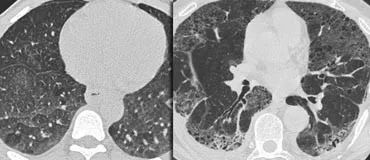

下图2例GGO,左侧无纤维化,可治疗;右侧伴牵引性支气管扩张,提示纤维化,不可治愈。

下图是以GGO为主导模式的病人。

此外,还有牵张性支气管扩张,表明存在纤维化。

本例为非特异性间质性肺炎(NSIP)的可能模式之一。

NSIP组织学特征是与不同程度的纤维化相关的细胞间质炎症的相对统一的模式。

与通常的间质性肺炎(UIP)一样,它主要累及下叶的依赖区,但NSIP缺乏蜂窝状的广泛纤维化。

NSIP可能是特发性疾病或与胶原血管疾病或接触药物或化学品有关。

NSIP的预后相对较好,大多数患者对糖皮质激素治疗有反应。

这一结果与UIP的结果有很大的不同,UIP的预后很差。